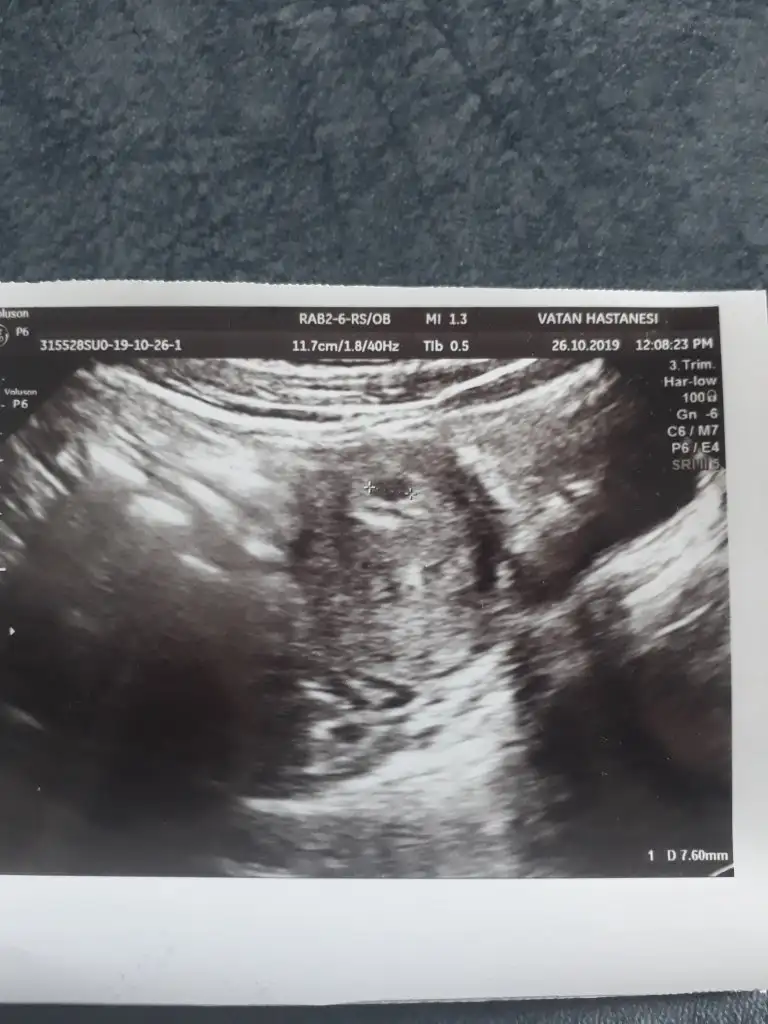

• 15721765558145533106961632283917.webp

37 KB · Görüntüleme: 59